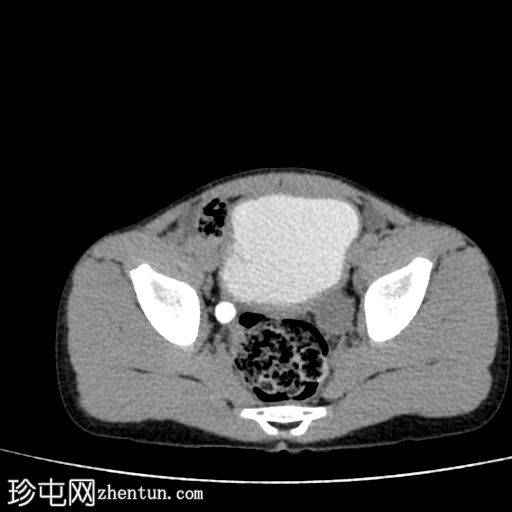

轴位

平扫

1.jpg

在这张多期增强CT图像中,我们可以观察到肾盏、肾盂以及左侧输尿管全程扩张。

未见感染或其他相关征象。